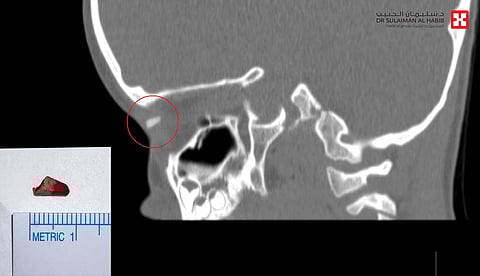

وأوضح أن نتائج الفحوصات كشفت عن وجود جسم غريب بطول 1 سم وعرض 4 مللم، في محجر العين اليمنى، بالمنطقة الواقعة ما بين العظم والعين، مع عدم وجود أية عدوى أو التهابات وسلامة المقلة.. وعلى الفور تم التدخل الجراحي العاجل؛ وذلك للحيلولة دون إصابة الطفل بالعدوى، أو حدوث أية مضاعفات قد تصل إلى فقدان الرؤية لا سمح الله.

وأكد أنه عقب اتخاذ كل التدابير اللازمة، أخضع الطفل لعملية جراحية استغرقت 35 دقيقة تحت التخدير الكامل، تم فيها استئصال الجسم الغريب وتنظيف مكان الجرح، نُقِل بعدها الطفل إلى جناح التنويم. كما تَبين من المعاينة للكتلة أنها قطعة خشبية عبارة عن بقايا قلم تلوين كان الطفل يلهو به.